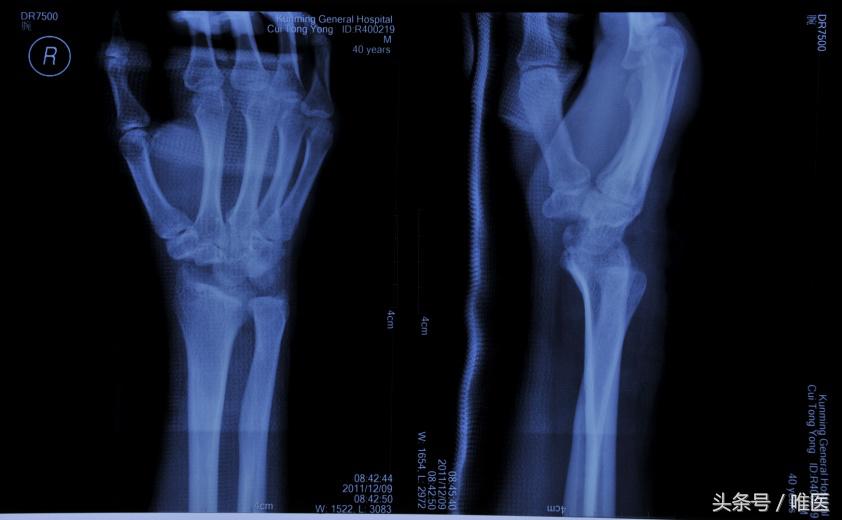

经舟骨月骨周围脱位,是指合并有舟骨骨折的月骨周围脱位,舟骨近端骨折块和月骨与桡骨远端关节面关系正常,而远端骨折块和其他腕骨一起发生脱位,可分为背侧脱位和掌侧脱位。

经舟骨月骨周围骨折脱位是腕部少见的严重损伤,占腕部损伤的3%-5%,多以背侧脱位为主,早期漏诊及误诊率极高,后期常发生舟骨骨不连、舟骨坏死、腕不稳定、创伤性关节炎等并发症,严重影响腕关节及手的功能,治疗上较为困难。对于经舟骨月骨周围脱位的治疗不仅要恢复腕关节正常的解剖结构,而且要确保舟骨骨折的愈合,避免发生舟骨坏死。